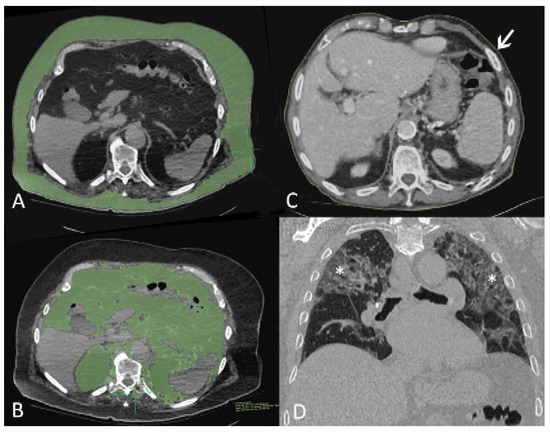

2.3. CT Scans Acquisitions, Interpretation and Quantification